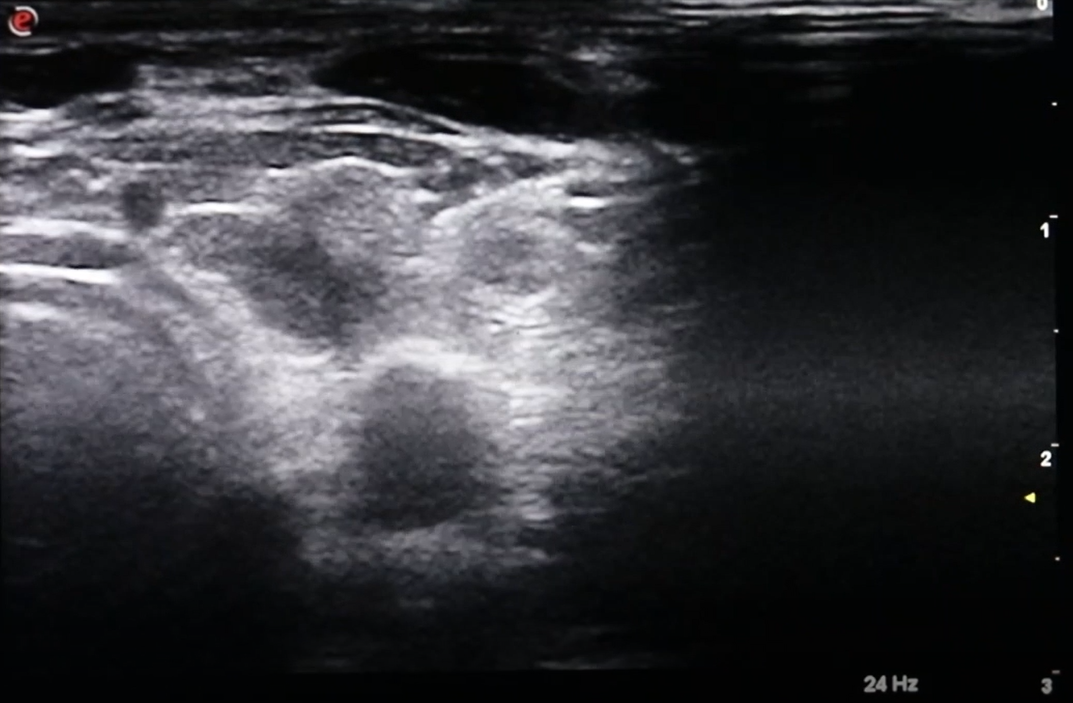

This case shows effect of 2 treatments on a large nodule and the correlation between volume reduction and normalization of thyroid levels

Ablation is accomplished by the dissipation of heat (produced by high-frequency radio waves) from the tip of a special water-cooled needle. Specialized white blood cells subsequently remove the dead nodule tissue in the weeks, and months following RFA, which causes the nodule to shrink considerably. Large-scale studies have shown an average reduction in nodule volume of approximately 60% after 3 months, and of 80% after one year, depending on the original nodule size and composition.

As the volume of the nodule decreases, complaints including: swallowing problems, pressure sensation, and feelings of constriction in the throat are reduced, as the visible bulge in the neck disappears.